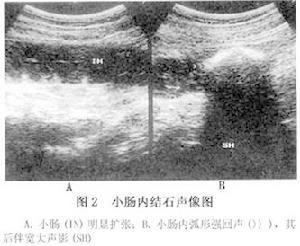

3.B超檢查可見到腸腔內有強烈的食糜反流和弧形不均質的強回聲帶,回聲帶後方有遞次衰減的聲影(圖2)。